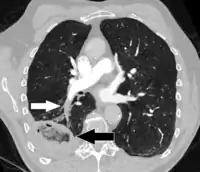

Large saddle embolus seen in the pulmonary artery (white arrows).

Fewer than 5 to 10% of symptomatic PEs are fatal within the first hour of symptoms.[36][90]